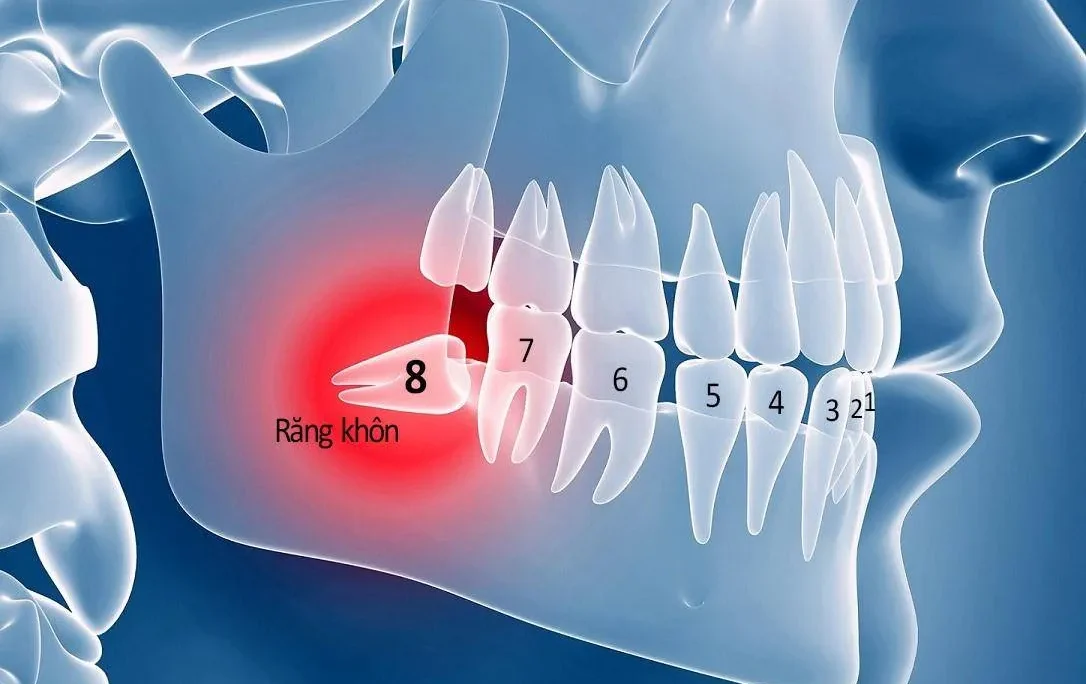

Răng kẹ hay còn gọi là răng thừa, răng mọc sai vị trí, mọc chen chúc với những chiếc răng khác. Răng kẹ có thể mọc một hoặc nhiều chiếc, khiến hàm răng kém thẩm mỹ, gây ra các bệnh lý nguy hiểm cho răng. Vậy răng kẹ phải làm sao, có nên nhổ răng kẹ hay không? Cùng Nha khoa Dr Green tìm hiểu hiểu và đưa ra phương pháp xử lý phù hợp cho hàm răng của bạn.

Nguyên nhân hình thành răng kẹ? Răng kẹ có nguy hiểm không?

Răng kẹ ảnh hưởng thế nào tới răng miệng?

Răng kẹ khiến nụ cười kém tự tin hơn, nguy cơ dẫn tới các bệnh lý nguy hiểm và làm thay đổi cấu trúc răng. Cụ thể:

Nguy cơ cao mắc các bệnh lý về răng

Răng mọc ở vị trí bất thường sẽ cản trở việc ăn nhai, thức ăn dễ kẹt lại trong kẽ răng và khó làm sạch. Lâu dần hình thành mảng bám cứng đầu, ổ vi khuẩn nguy hiểm, nguy cơ cao mắc viêm nướu, sâu răng…

Thay đổi cấu trúc răng

Răng mọc chen chúc, sai vị trí sẽ làm ảnh hưởng tới những chiếc răng kế cận. Lâu dần dẫn tới sai lệch khớp cắn, làm thay đổi cấu trúc răng.